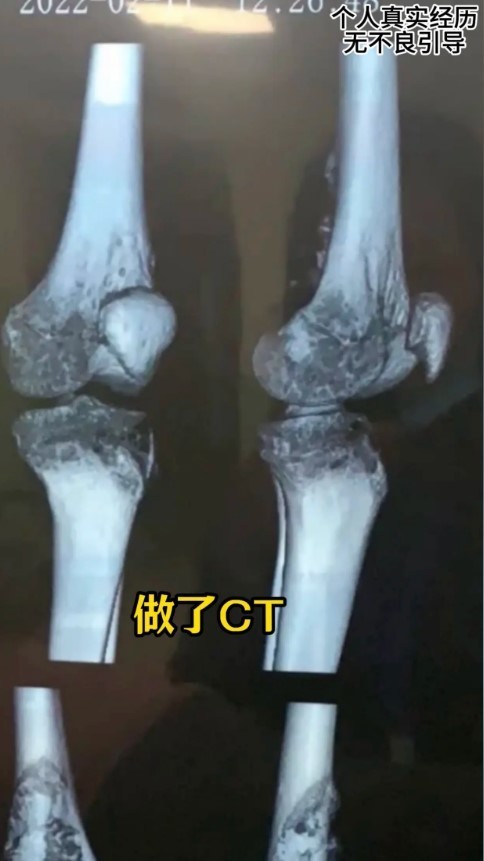

綜合內媒報道,年僅15歲的王子晟,在升上高中時,經常感到腳部疼痛。起初他的母親以為是生長痛,帶他去針灸治療,但效果不佳。隨著疼痛加劇,他經常在半夜痛醒,家長才意識到情況的嚴重性,於是連夜前往當地醫院檢查,最終懷疑患上骨肉瘤,隨後在上級醫院確診。

確診後,王子晟開始接受化療。不過,經過一段時間,醫生建議他進行截肢,幸運的是,他通過手術勉強保住了腿部,但留下了一條長達43厘米的「蜈蚣」疤痕。